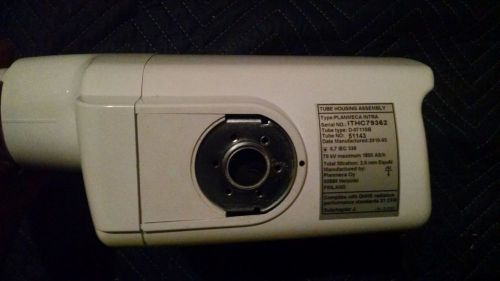

PLANMECA INTRA XRAY TUBEHEAD 2010 LITTLE USE